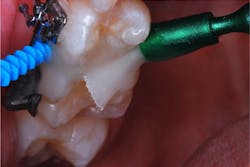

The patient returned for a routine recall appointment on April 6, 2021, wearing fixed orthodontic hardware. A bitewing radiograph was taken (figure 2, top right). The site was cleared with floss, and a new pick soaked with SDF was inserted (figure 3). A small applicator was used to paint sluiceways to enhance the flow of SDF. The pick was slid in and out of the interproximal surfaces a few times (figure 4). The treatment site was immersed in 5% fluoride varnish (figure 5).